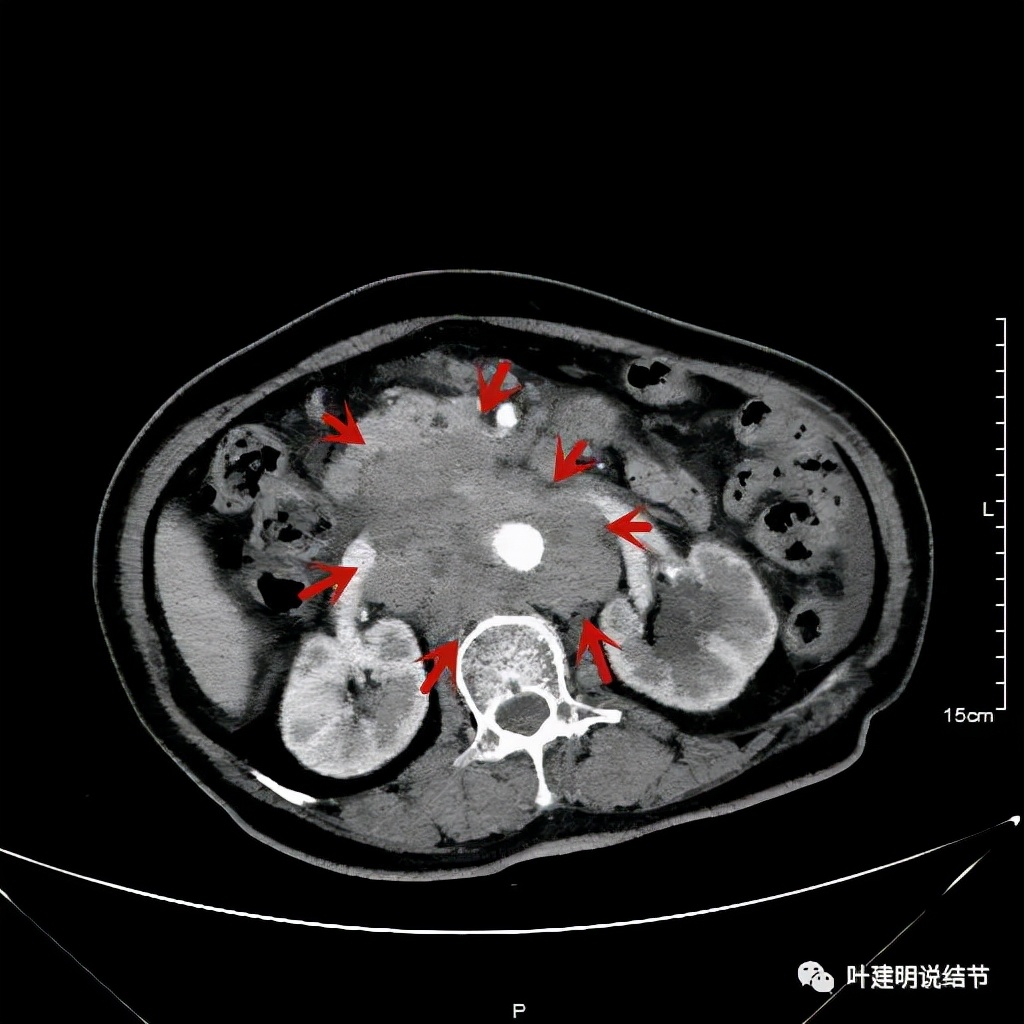

上图同样左侧是治疗前的,右侧经过2周期免疫加化疗后复查的,可见病灶缩小甚至超过9成。下面是治疗前与后来于6月底复查的:

可见经过4个多月的治疗,转移灶已经几乎看不出来了!目前患者无任何不适,正常进食,也无腹部症状或体征,仍在持续特瑞普利单抗维持治疗中。我们期待其更长久的获益与持久的疗效,为其他晚期食管癌积累自己的实战经验(开会或文献上别人的介绍没有自己遇到的如此直观,也没有如此深的印象。所以我一直觉得临床经验,尤其自己亲身经历积累的经验才更有说服力,也更有感受)。